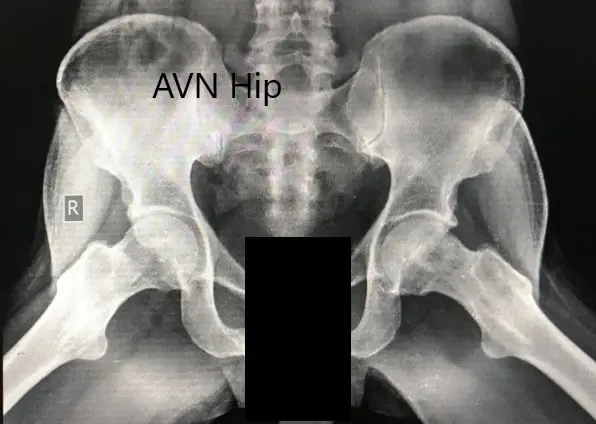

Imaging studies in the form of an X-Ray was obtained which suggested sclerosis of the bilateral head of the femur with acetabulum changes. An MRI was obtained which suggested avascular necrosis of both hips.

Preoperative X-ray of the pelvis with both hips in the frog-legged lateral view showing AVN of the bilateral hips.